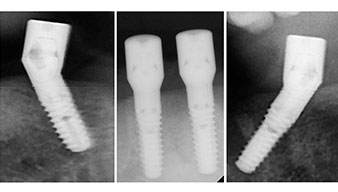

È stata eseguita una tomografia computerizzata Dentale Cone Beam in 3D (CBCT, con Planmeca) per aiutare la programmazione dell'intervento e la riduzione di rischi. L'esame ha evidenziato che la qualità e quantità dell'osso disponibile era sufficiente per eseguire l'intervento e la ricostruzione immediata, utilizzando il metodo Fast & Fixed. In base al protocollo del sistema, gli impianti sono stati inseriti in posizione 35, 32, 42 e 45. Gli impianti distali vengono installati a un angolo massimo di 45 gradi. Così facendo, il profilo che ne risulta viene spostato in posizione posteriore, generando un poligono di supporto più ampio (Fig. 3).

metodo Fast & Fixed

Fig. 3